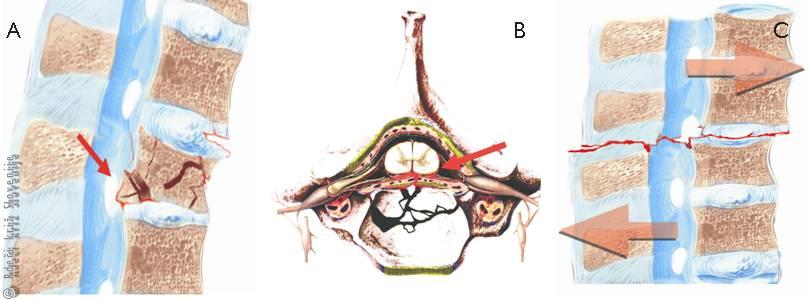

Slika 6

A – Najpogosteje se zlomi telo vretenca pri padcu na glavo ali zadnjico.

B – Kostni odlomki lahko poškodujejo hrbtenjačo.

Slika 7

Hrbtenjačo lahko poškodujejo kostni odlomki (A), medvretenčna ploščica (B), redkeje se zgodi, da se zaradi strižnih sil hrbtenjača nategne ali celo pretrga (C).